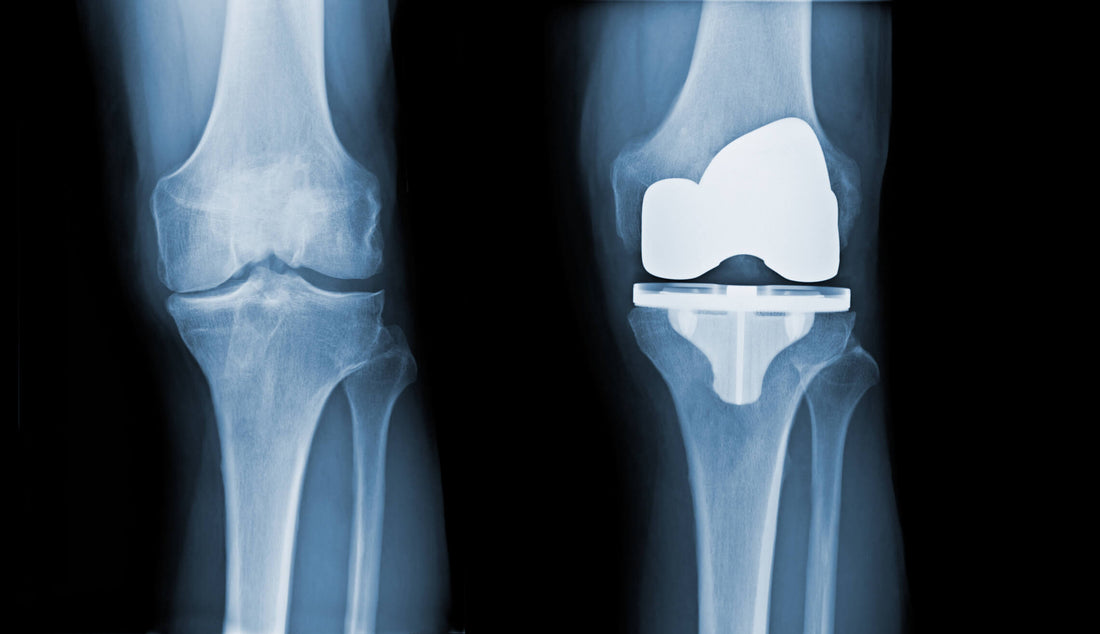

"How long will my new knee last?" It's one of the most common and important questions we hear in Physiotherapy clinics. Until recently, the answer was based on limited data. Now, a landmark systematic review and meta-analysis published in The Lancet provides one of the most comprehensive answers to date, analysing data from over 300,000 knee replacements.

The Bottom Line: The research found that 82% of total knee replacements (TKRs) and 70% of partial knee replacements (UKRs) last for 25 years. However, the longevity of the implant itself may only be part of the story for long-term success.